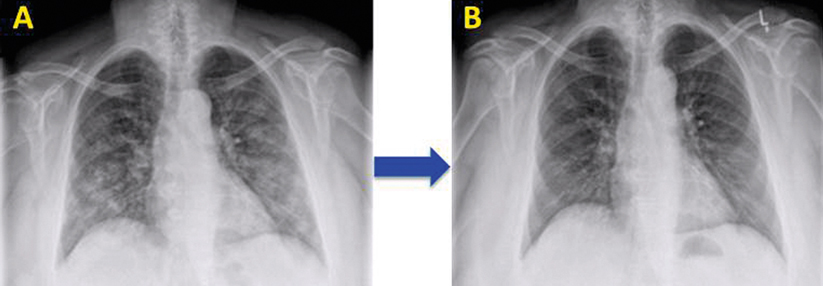

Lunge

• trockene oder feuchte Pleuritis (40–60 %)

• selten Lupuspneumonitis oder Lungenfibrose

Lunge/Herz

• Röntgenthorax

• hochauflösende Computertomographie des Thorax (HR-CT)